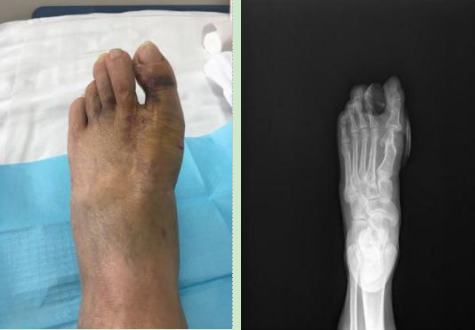

5. 女性,30岁,微创踇外翻术后对比图。